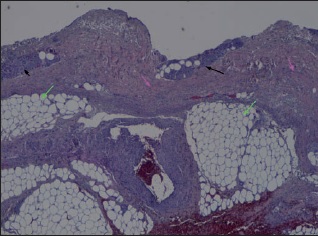

La realización de biopsias pre y postratamiento en 3 de los pacientes permitió observar 2 casos de desbridamiento parcial de la zona necrótica, siendo 1 caso una quemadura de tercer grado en dorso de mano que precisó de injerto (Fig. 25 a 34, caso 9), y el otro una quemadura previamente tratada con Flammazine Cerio® (Fig. 35 a 45, caso 12). En el tercero de los pacientes biopsiados apreciamos desbridamiento histológico completo de la zona necrótica con preservación de la dermis sana (Fig. 46 a 50, caso 11). Como hallazgos significativos, en las 3 muestras postratamiento evidenciamos un infiltrado inflamatorio linfocítico perivascular (Fig. 36, 40 y 48).

Uno de los aspectos más interesantes y novedosos de nuestro estudio son los hallazgos de los estudios histopatológicos. Una de las ventajas que parece tener Nexobrid® es la facilidad para el diagnóstico visual de la profundidad de la quemadura, que enlaza con la posibilidad de cubrir con injertos aquellas quemaduras que ya vemos que son de tercer grado, permitiendo un tratamiento conservador en aquellas zonas donde existe dermis viable. Nuestras 3 biopsias muestran una correlación del 100% con el diagnóstico clínico de profundidad de la quemadura tras el desbridamiento enzimático. Este diagnóstico no lo pudimos realizar antes de la aplicación del producto, ya que eran zonas de profundidad indeterminada, difíciles de valorar clínicamente antes del desbridamiento enzimático. Presentamos esta conclusión como uno de los puntos fuertes del tratamiento enzimático, ya que además de las implicaciones de la eliminación precoz de la escara, la facilidad de diagnóstico visual de la profundidad de la quemadura podría implicar un abordaje más fácil de las lesiones a la hora de decidir si injertar o si esperar a la epitelización espontánea.

Si bien planteamos la realización de las biopsias para comprobar la correlación clínico-histológica del diagnóstico de profundidad de la quemadura, evidenciamos una disparidad de criterio en la eficacia del desbridamiento según se considere el aspecto clínico o el histológico. Así, aunque nos pareció clínicamente que el desbridamiento fue completo en todos los casos, constatamos mediante la histología que no era así. Dos de las 3 muestras presentaron desbridamiento histológico incompleto. Sin embargo, 1 de ellas fue una quemadura de tercer grado que precisó injerto y en la que la reaplicación del producto no hubiese supuesto ninguna ventaja; en la otra, la quemadura epitelizó espontáneamente sin necesidad de mayor desbridamiento, por lo que nuevamente la reaplicación no parece que hubiese supuesto ventajas añadidas. De estos resultados podemos deducir que la valoración clínica de la eficacia del desbridamiento, aunque no coincide con la valoración histológica y tiende a sobreestimar la capacidad desbridante de Nexobrid®, sí parece suficiente para decidir la reaplicación del producto, sin precisar biopsias que determinen la eficacia del desbridamiento.

Otro hallazgo significativo de nuestro estudio es el incremento del infiltrado inflamatorio tras el tratamiento (Fig. 36, 40 y 48). Sin embargo, no podemos afirmar que sea consecuencia del tratamiento enzimático ya que no realizamos comparación con zonas de quemadura no sometidas a tratamiento con Nexobrid®. Además, en la literatura existe referencia al infiltrado neutrofílico típico que existe en la zona intermedia de la quemadura (región histológica comprendida entre la zona sana y la zona necrótica de la quemadura), pero el evidenciado en nuestro estudio es un infiltrado linfocítico perivascular que, hasta donde nosotros sabemos, no aparece mencionado en ningún estudio publicado sobre el desbridante Nexobrid®.(21) Aunque desconocemos si este infiltrado es originado o potenciado por el tratamiento con Nexobrid® o bien debido exclusivamente a la progresión de la quemadura, sería necesario estudiar si el posible incremento del infiltrado inflamatorio guarda correlación con la velocidad de curación o con el pronóstico a largo plazo, o bien es únicamente el resultado de la evolución fisiopatológica de la quemadura y no existen diferencias con el infiltrado evidenciado en las quemaduras no tratadas con Nexobrid®.